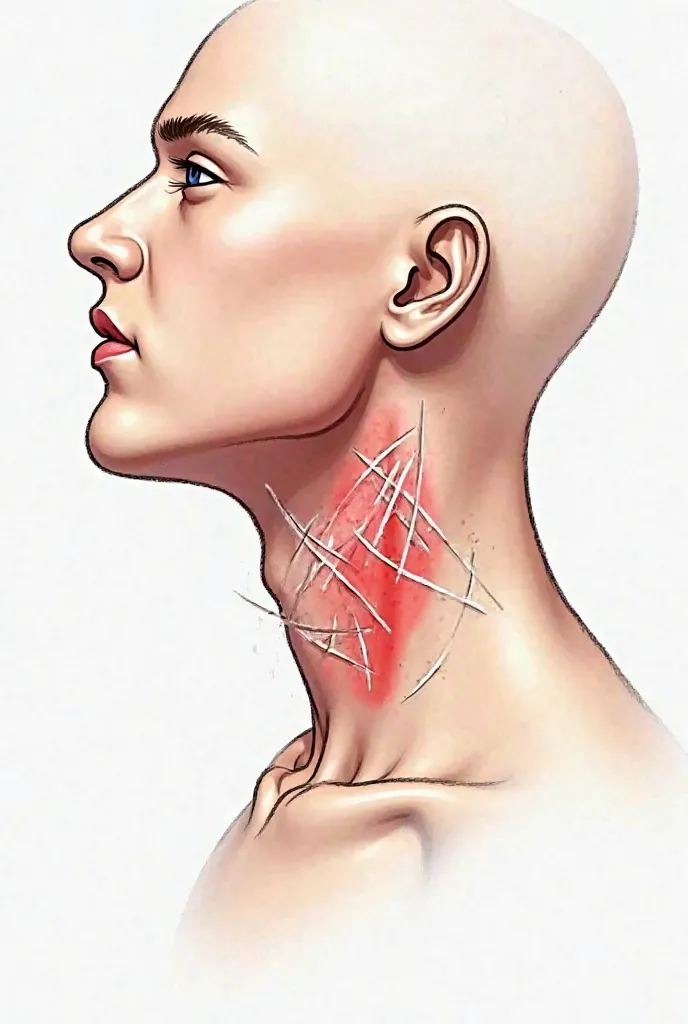

Pictures of swollen thyroid gland in neck, Use a Canon EOS 5D Mark IV with a 24

pictures of swollen thyroid gland in neck, Use a Canon EOS 5D Mark IV with a 24-70mm f/2.8 lens. Settings: ISO 100, aperture f/8, and shutter speed 1/125s to capture a sharp, vibrant image with a wide depth of field.

pictures of swollen thyroid gland in neck